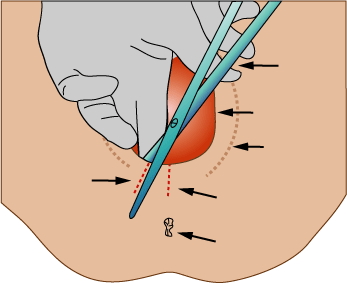

CESÁREA:

Extracción del feto, placenta y membranas ovulares a través de una incisión practicada en la pared abdominal y en el útero de la madre

Extracción del feto, placenta y membranas ovulares a través de una incisión practicada en la pared abdominal y en el útero de la madre